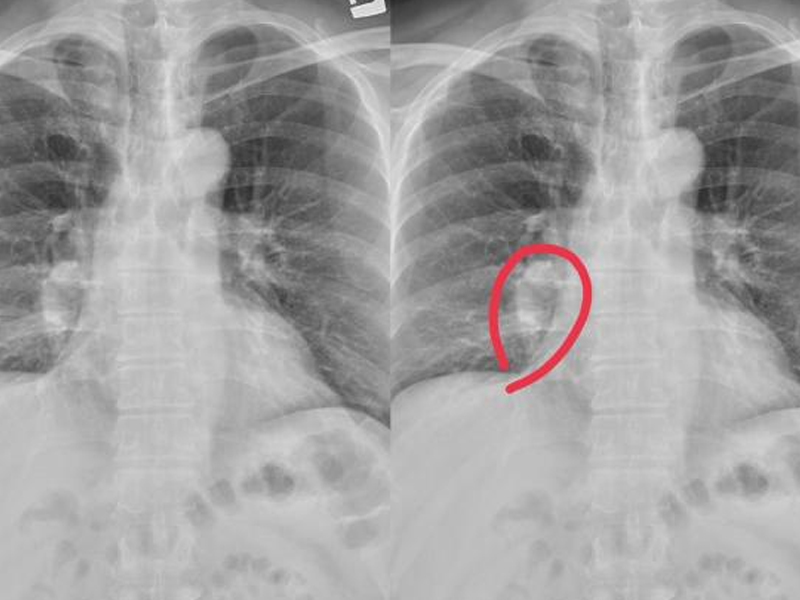

瀏覽:2206 很多男人好奇,壯陽保健品有哪些,又有什麼分別? | 瀏覽:897 壓力與衰老:這 3 種跡象揭示你的健康隱患 | 瀏覽:4266 腿部有這 4 個症狀,高度懷疑是肺癌 |